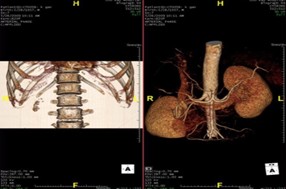

Những năm vừa qua được sự quan tâm của thủ trưởng các cấp cùng với sự đầu tư của Đảng ủy, Ban giám đốc Bệnh viện trong chẩn đoán và điều trị, bệnh viện đã trang bị nhiều máy móc hiện đại, trong đó đặc biệt có máy CT Scanner 16 Slice SIEMENS của Cộng Hòa Liên Bang Đức, cùng với sự chuyển giao kỹ thuật, công nghệ mới, các bác sỹ và kỹ thuật viên đã làm chủ hoàn toàn các kỹ thuật phức tạp mà chỉ có tuyến tỉnh và trung ương mới đáp ứng được như: Chụp CTscanner có thuốc cản quang gan ba thì, ổ bụng, lồng ngực, sọ não, hệ mạch máu bụng, chậu, chi…Trong thu dung cấp cứu, máy CT Scanner càng phát huy thế mạnh trong chẩn đoán chấn thương sọ não, chấn thương bụng kín…